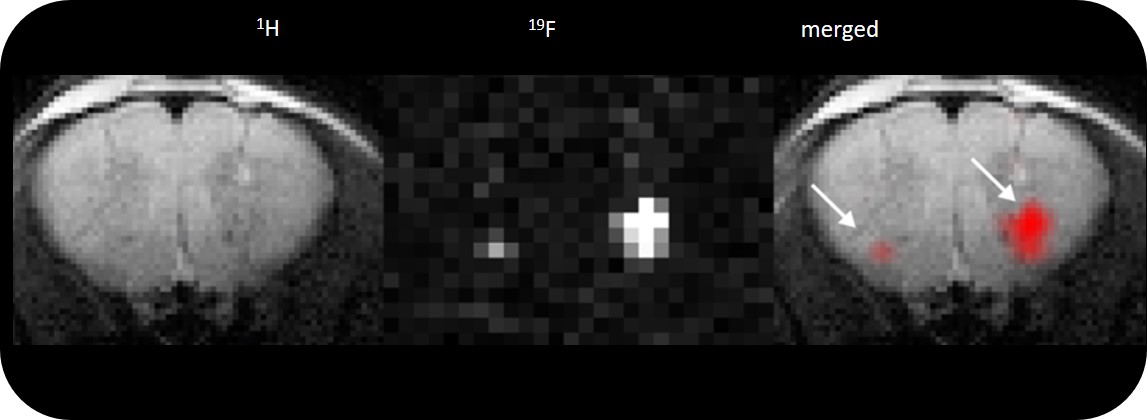

• Complete RF coil portfolio for mice and rats available, including coils for head, brain, cardiac, spine, body, multi-channel array coils with up to 8 channels, and x-nuclei

• MRI CryoProbe for exceptional increase in sensitivity